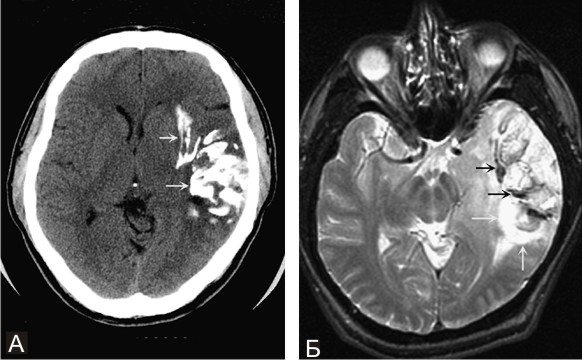

Магнитно-резонансную томографию (МРТ);

Компьютерную томографию (КТ);